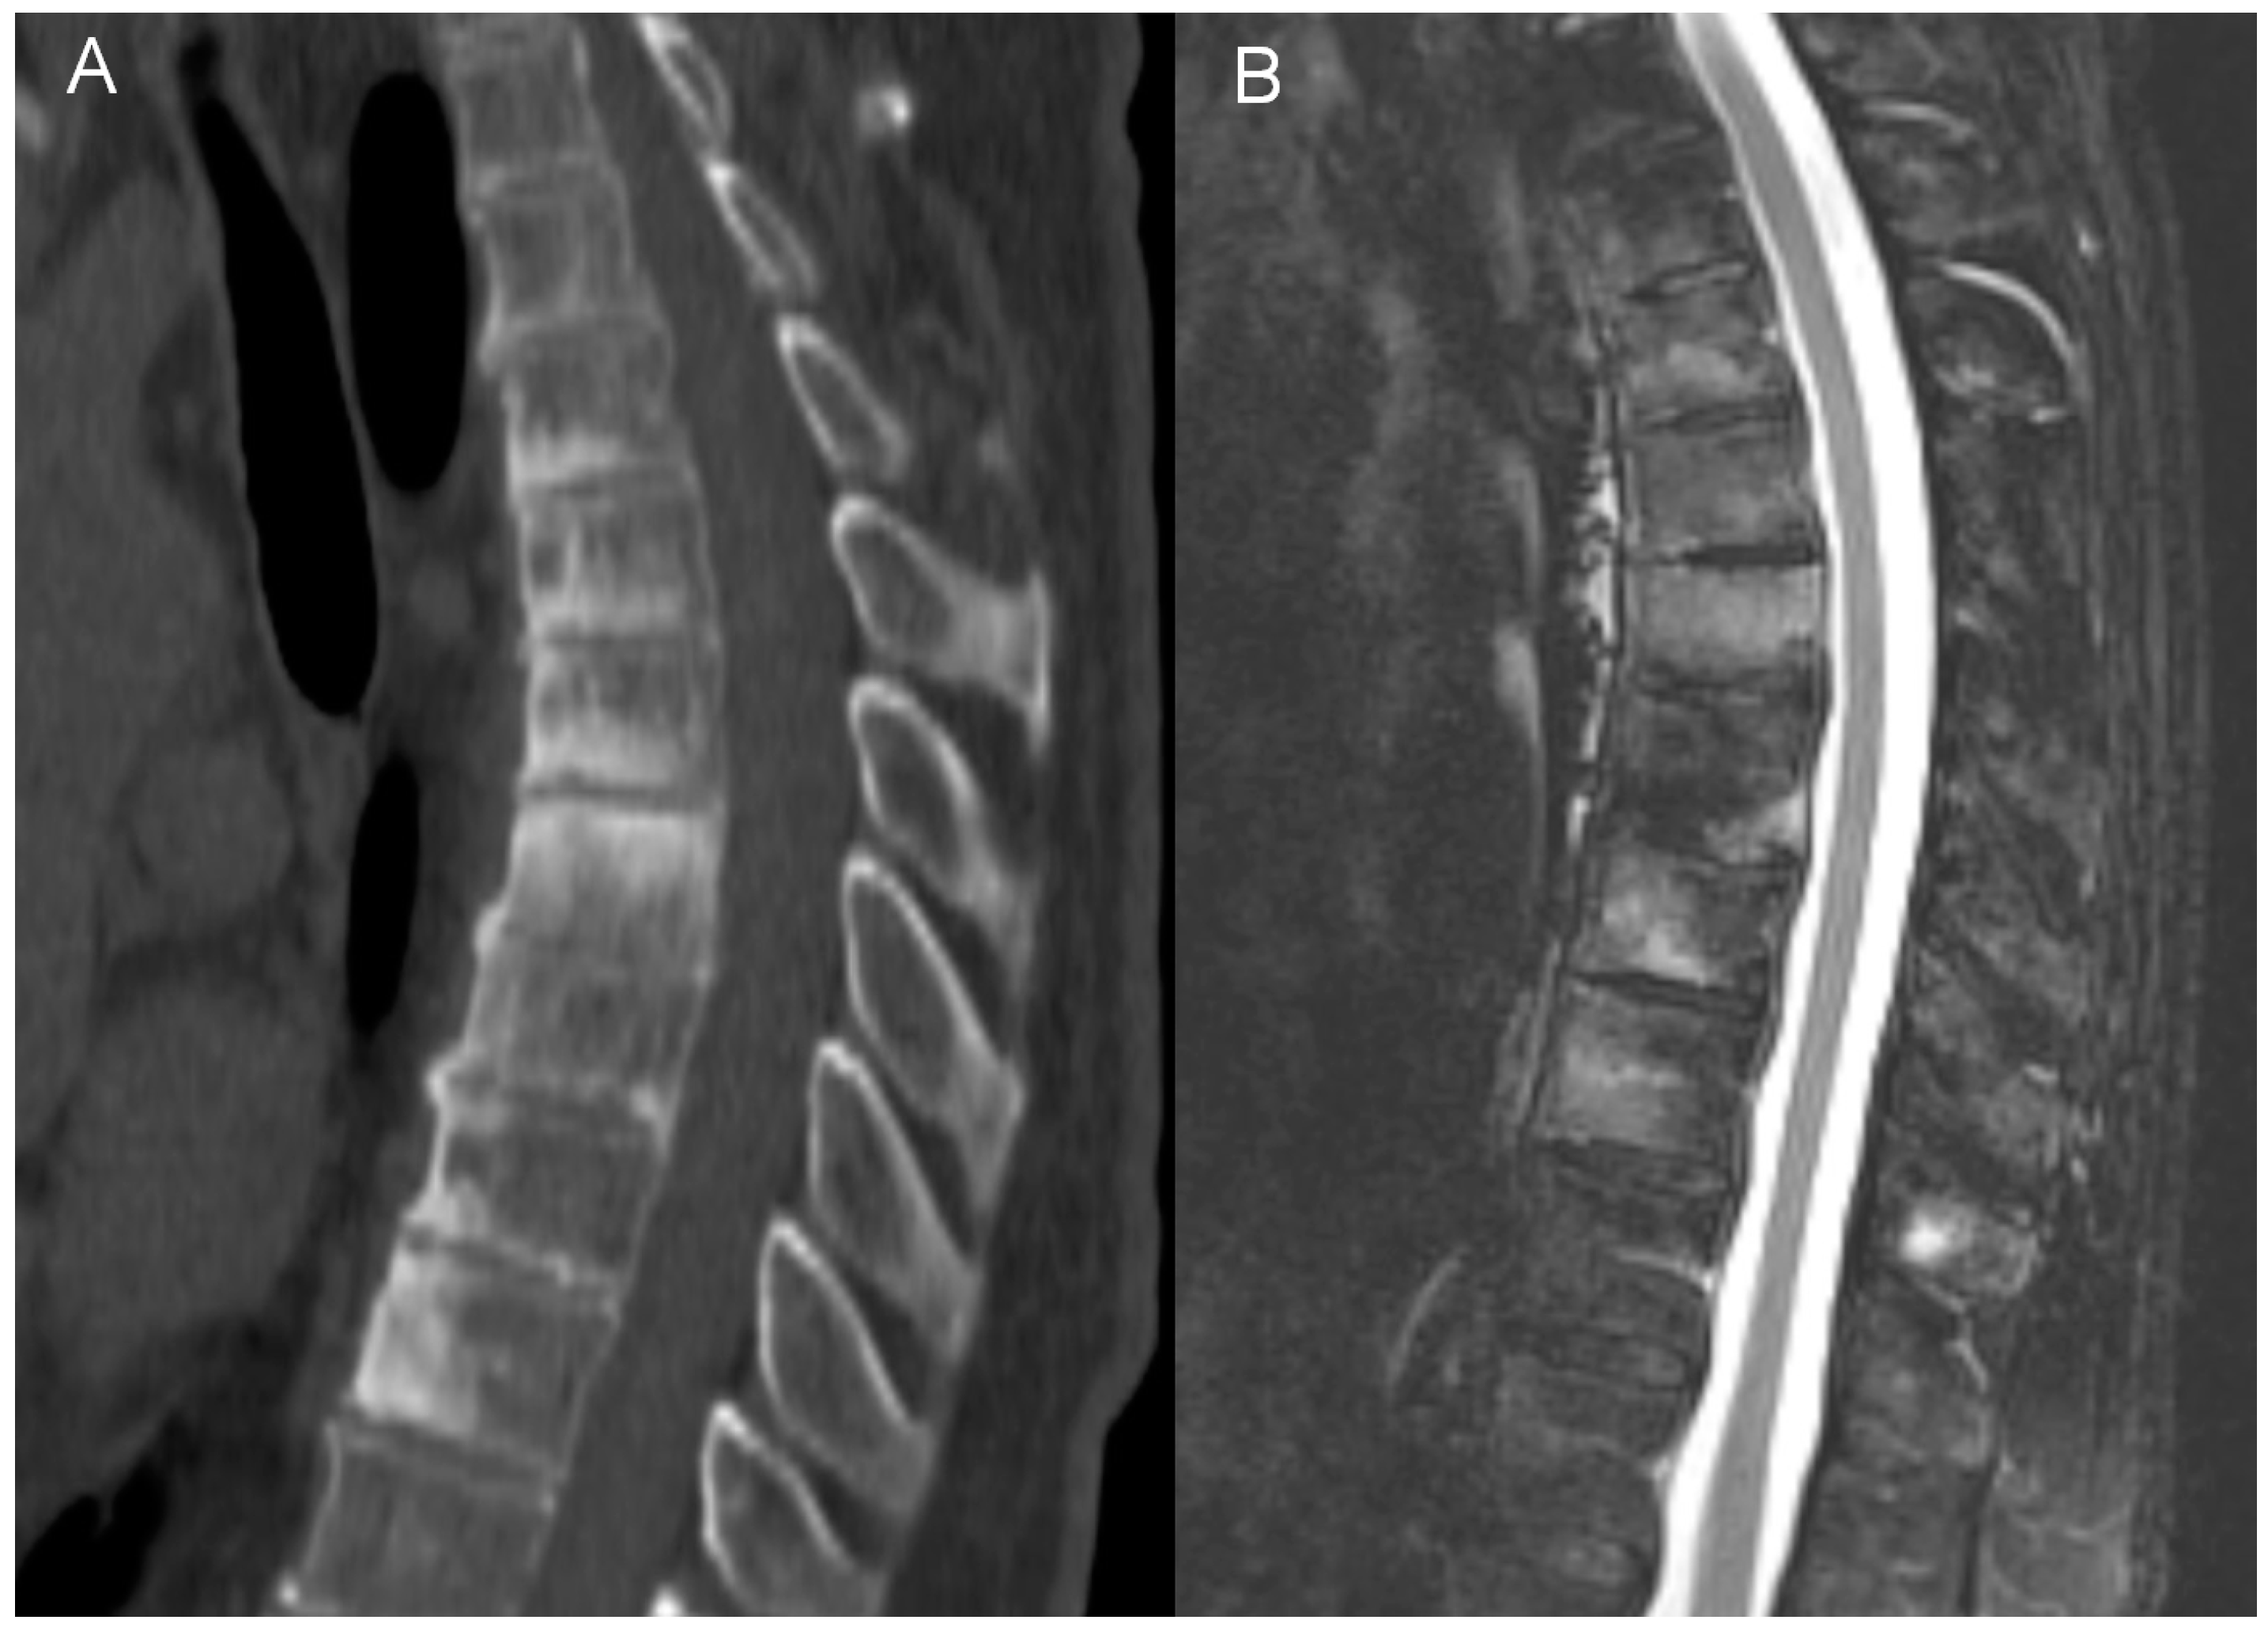

- bone marrow edema (BME) presence and pattern (Figure 1):

Figure 1. Bone marrow edema (BME) patterns appreciated on T2 FS/STIR MRI images. (A). corner inflammatory lesions (arrow); (B). propagating (arrowheads); (C). semicircular/curvilinear (dotted line); (D). diffuse—patchy (in the upper two vertebrae) and solid (in the lowest vertebra).- vertebral body corner inflammatory lesions (CIL)—active Romanus lesion defined as small foci of BME at the vertebral corners,

Bone marrow edema (BME) was present in all 12 patients who underwent MRI. Different patterns of BME coexisted: in most patients, diffuse vertebral body BME was seen (67%), followed by BME propagating along the endplates (50%) and CIL (40%). Semicircular pattern of BME was observed in three patients (25%), However, it involved the highest number of vertebrae (Table 3).